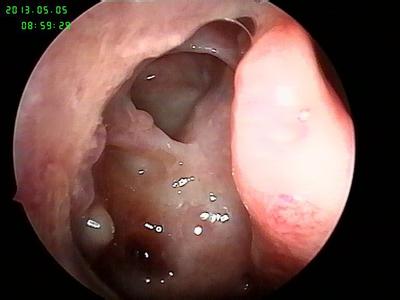

鼻息肉圖片

鼻息肉